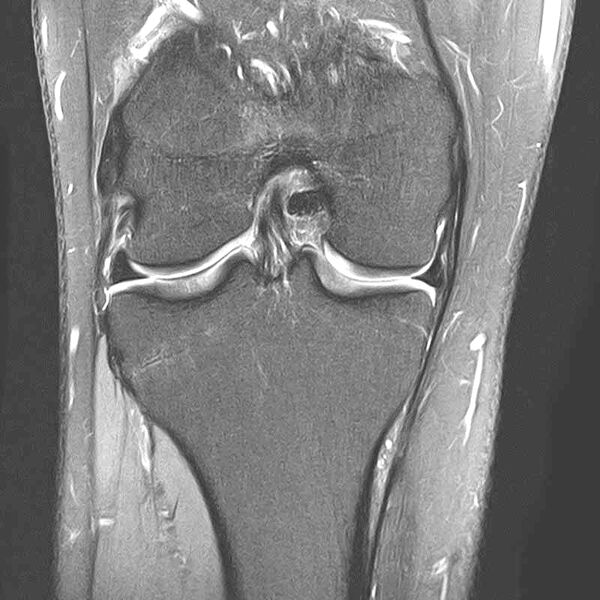

. Ein CT-Scan der Lunge in zwei Ansichten, mit farbcodierten Bereichen zur Darstellung der Gewebedichte.

Perfusionsstudie mit Dokumentation Embolie-bedingter Mikrozirkulationsstörungen (blau)